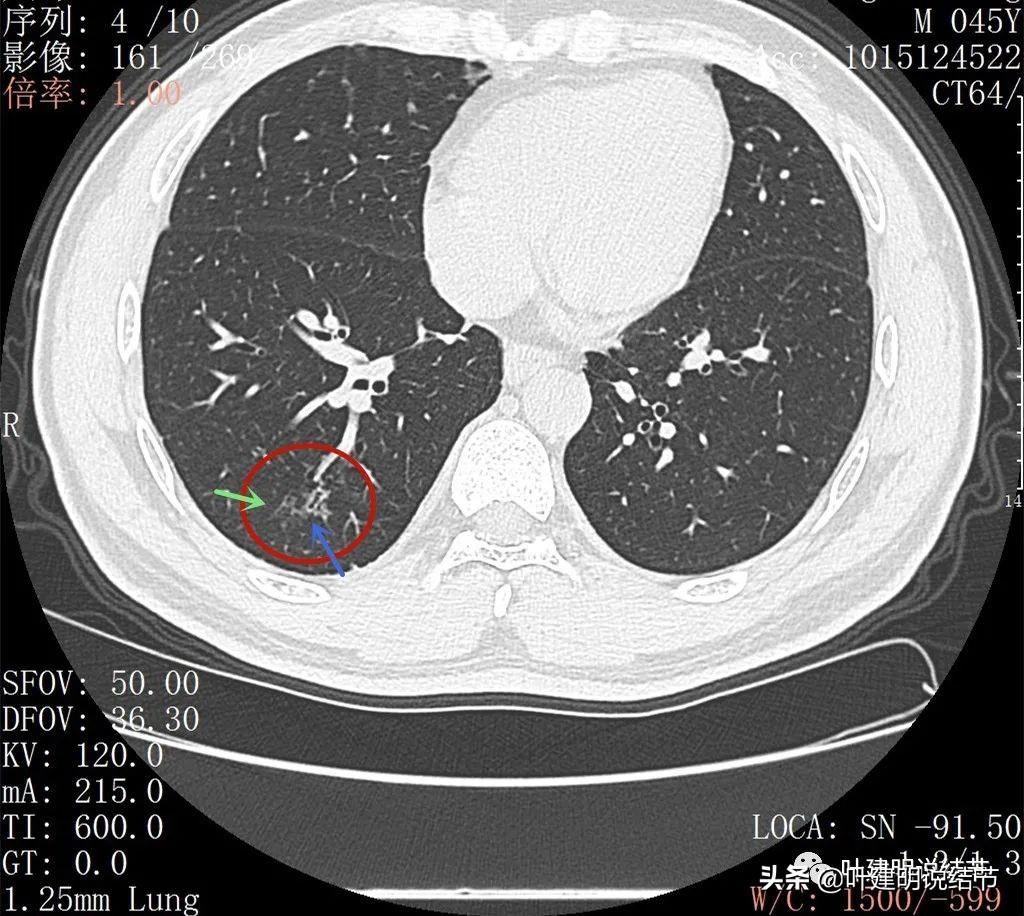

右下叶背段有散在斑点状病灶,形态类似,但较主病灶小得多;左侧也有小结节状。

邻近病灶的下叶背段处也有形态类似的病变

因靶扫描与后来复查的变化不明显,后文展示2022年5月份的靶扫描图像。